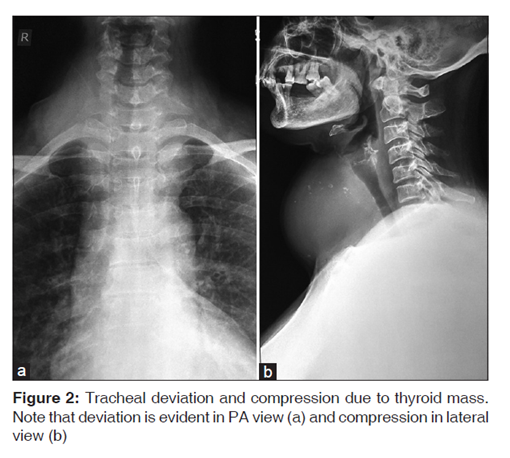

1.气管内导管定位的确认[图1]。

(X射线下单侧插管的测定。)